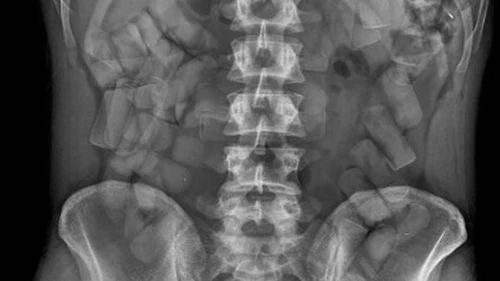

Un hombre que llevaba en su estómago 105 cápsulas de cocaína fue detenido en el aeropuerto internacional de Ezeiza junto a otras cuatro personas, informaron fuentes policiales a Online-911. Se trata de un ciudadano argentino domiciliado en la localidad bonaerense de Glew y se encuentra internado en el Hospital Zonal “Alberto Antranik Eurnekian” de ese partido.

Una vez recabada la cantidad necesaria de pruebas, aprovechando el conocimiento de que ayer se enviaría un cargamento de droga, se intervino con el personal de la División Operaciones Metropolitanas con auxilio de un equipo de rayos “X” denominado “Body Scan”. Aunque sabían que contendrían envoltorios de cocaína dentro de su cuerpo, los efectivos se vieron sorprendidos al observar la gran cantidad de cápsulas, ya que están acostumbrados a un número menor.